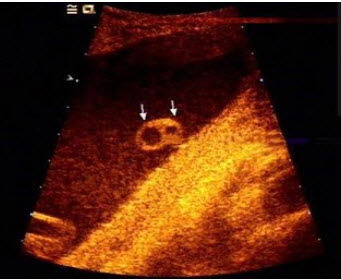

E.以上都不是

如图,为一孕妇34周时,羊水内漂浮所见管道结构(横切),最可能的诊断是()

A.脊柱裂

B.脑膜膨出

C.淋巴管囊肿

D.单脐动脉

E.正常图像